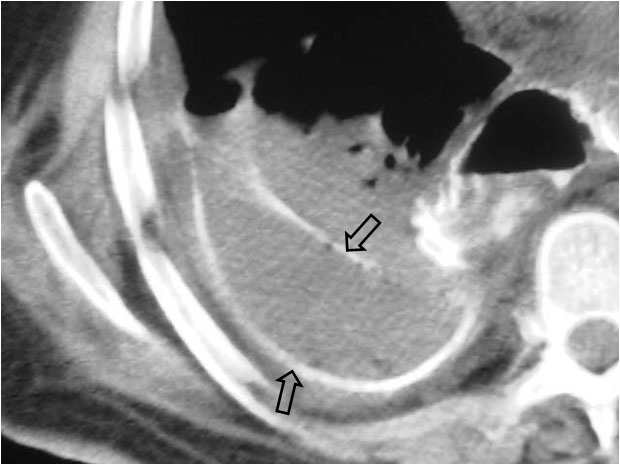

Cuando en la TC vemos que las cruras diafragmáticas están desplazadas lejos de la columna por líquido, éste está situado en la cavidad pleural (flecha). El líquido intraabdominal, a diferencia del derrame pleural, se sitúa lateral y anterior a las cruras.